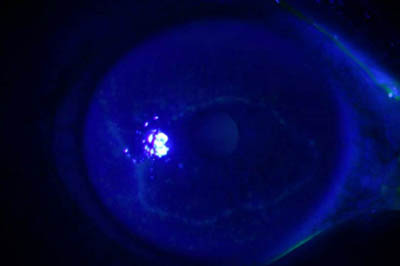

• Microscopia Confocal : 94 a 100% de especificidad y 80 a 84% de sensibilidad

Microscopía Confocal

Dendritas Herpéticas Dendritas Herpéticas